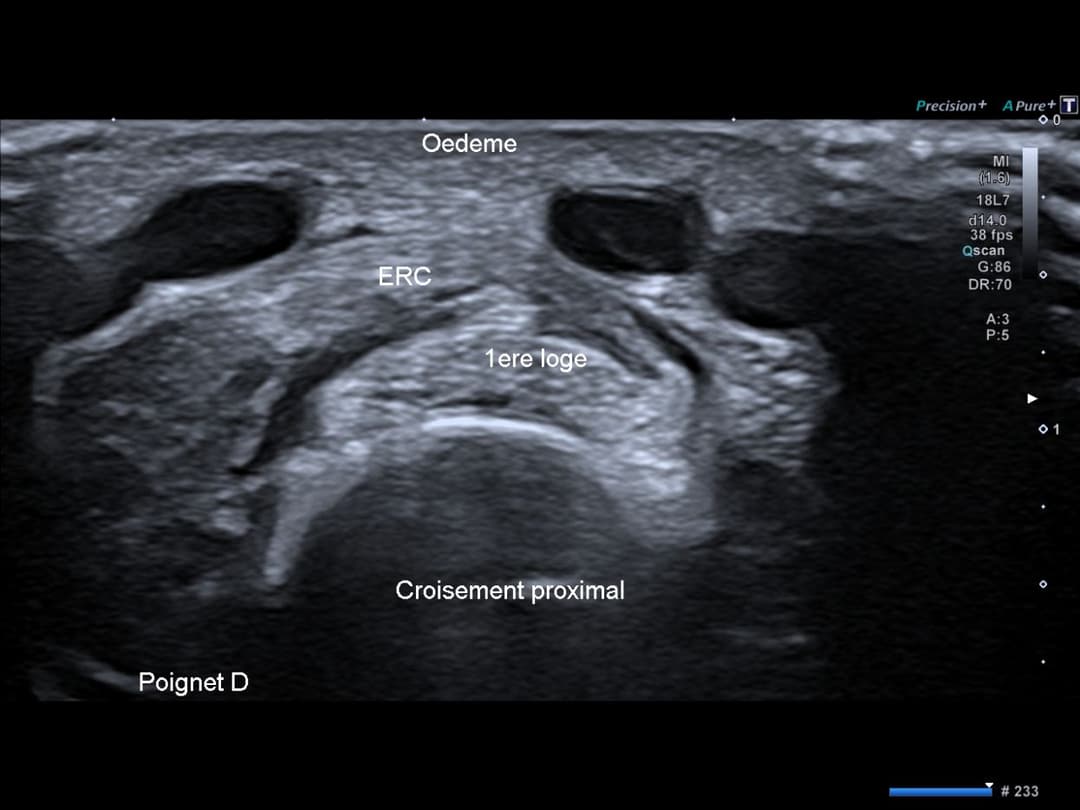

Congestion œdémateuse des parties molles en regard du croisement tendineux entre d'une part les tendons court et long extenseurs du carpe et d'autre part les tendons du premier compartiment tendineux (court extenseur du pouce et long abducteur du pouce).

Congestion œdémateuse en regard de la zone de croisement proximal